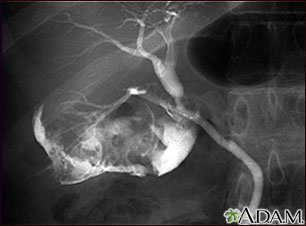

Colangiograma de una colecistitis

La colelitiasis se puede ver en un colangiograma. Se utiliza tinte radio opaco para mejorar la radiografía. En la vesícula biliar hay múltiples cálculos (PTCA).